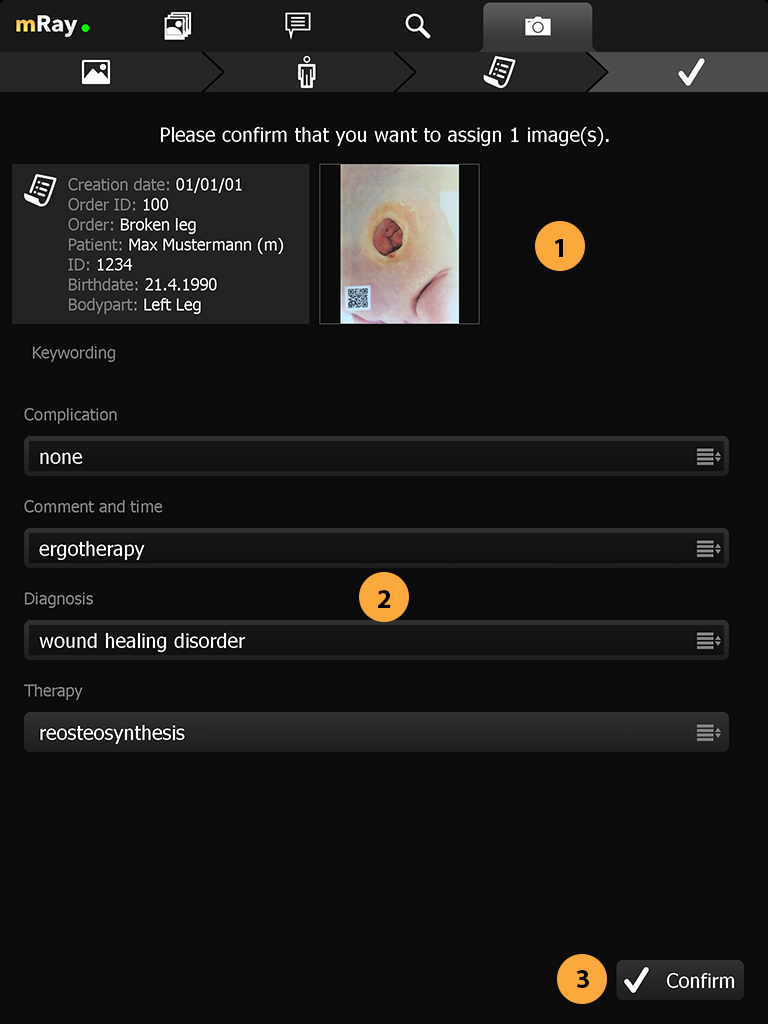

15.6. Confirmation view

In this step you have the ability to review your assigned photos one last time and to add additional tags to the order that can help with identifying the order at a later stage. (The keywording must be configured at the server to be available, please contact your administrator or mbits support)

-

Preview of the added images and patient information.

-

Selection of further tags and information for the order.

-

Confirm inputs and proceed.